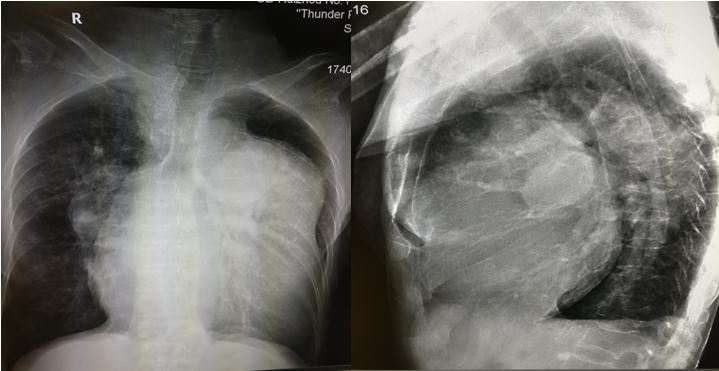

3.左心房增大

常见于二尖瓣病变特别是二尖瓣狭窄、左心衰竭、先心病如室间隔缺损等。见图3。

图3 二尖瓣换人工瓣膜后,左房增大